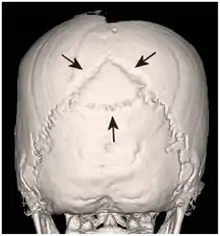

After these different views of the remains have been obtained, it is possible to create a three-dimensional reconstruction of the body. This brings into focus details which may have been missed on the axial imagining. Algorithm manipulation is used to create the rotational 3D images.[6][5] In paleoradiology, the 3D images provide a greater understanding of the remains themselves. For example, in 2002, a study of nine Egyptian mummies found that by using the 3D reconstructions they could see the preservation of soft tissues, such as the penis on one male body and braided hair on female remains. The 3D modelling also illustrated discrepancies between the remains, as some had their internal organs removed while others had not.[5]

A recent CT scan of Tutankhamun in 2006 was able to provide evidence against the 'homicide theory'.[2][6] A depression fracture noted on the skull from X-rays taken 30 years previously was found to be a post-mortem injury rather than a cause of death.[6] The hole in the head had been created in order to continue the embalming process of mummification.[10] This CT investigation was also able to confirm Tutankhamun's age of death as nineteen and disprove the idea that the young pharaoh had suffered from scoliosis; rather the bend in his spine was from additional post-mortem damage to the body.[10]